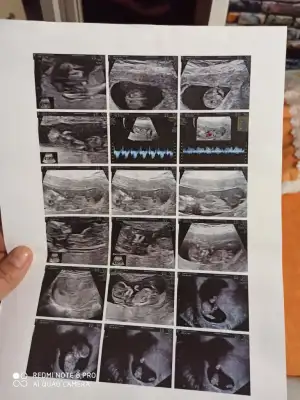

Merhaba bende Amerikan ve Koç hastanesi arasinda gidip geliyorum bu gün 14+1 oldum Allianz policem bitmiş mecbur Çarşamba günü çakmak erdem hastenesine gideceğim erkeğe benziyor demişlerdi bakalım netlesecekmi

Merhabalar,

Yorumları okudum genel olarak da neredeyse hepiniz hareketlerini hissediyorsunuz maşallah.

Ben 2. Hamileliğim olmasına rağmen hala bir şey hissetmiyorum 🤷‍♀️ Önümüzdeki cumartesi kontrolüm var bakalım ne diyecek